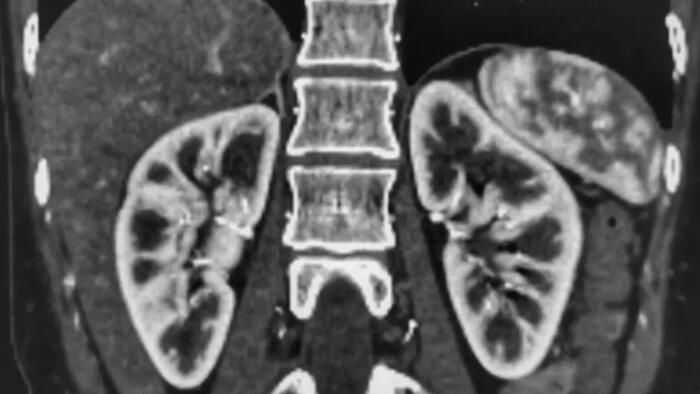

New Zealand Fudged The Data On How Kidneys Fare After COVID Vaccines | ZeroHedge